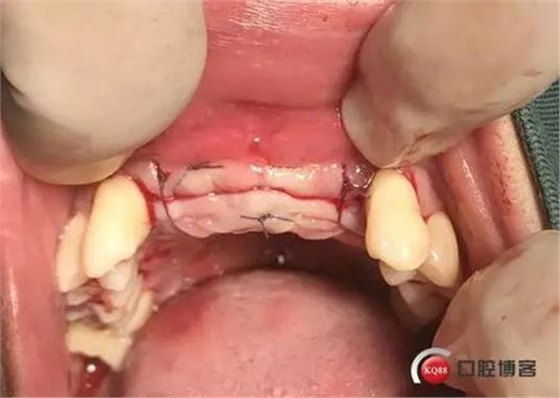

縫合完成

二期術(shù)后愈合附著齦寬度適中